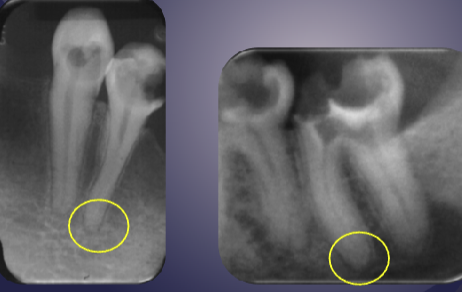

differentiate the pathology for #30 + #31

#30: apical rarefying osteitis

#31: developing tooth w/ open root apex

differentiate the pathology of the 2 images

left: loss of apical lamina dura + periapical radiolucency

right: normal lamina dura + radiolucency due to submandibular fossa